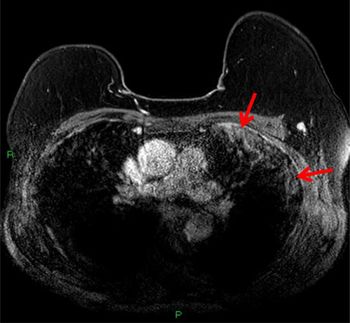

Suspicious lesions that develop during neoadjuvant therapy are uncommon, and they are highly unlikely to be malignant.